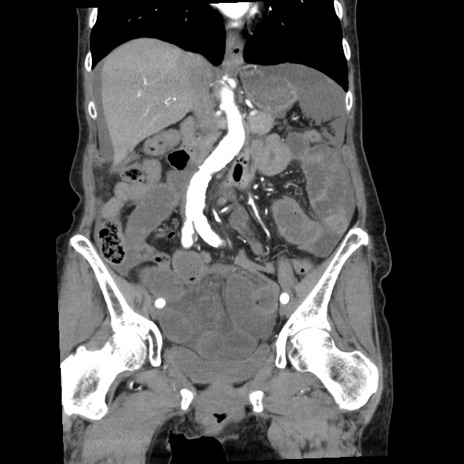

症例1(冠状断像)

【症例】80歳代女性

【主訴】腹痛

【現病歴】8時間前から腹痛あり来院。

【既往歴】糖尿病、脂質異常症、子宮体癌にて子宮全摘術

【身体所見】意識清明・会話良好だが腹痛で苦悶様、全腹部にわたって反跳痛と圧痛あり

【データ】WBC 13600、CRP 0.14、LDH 224、CK 90